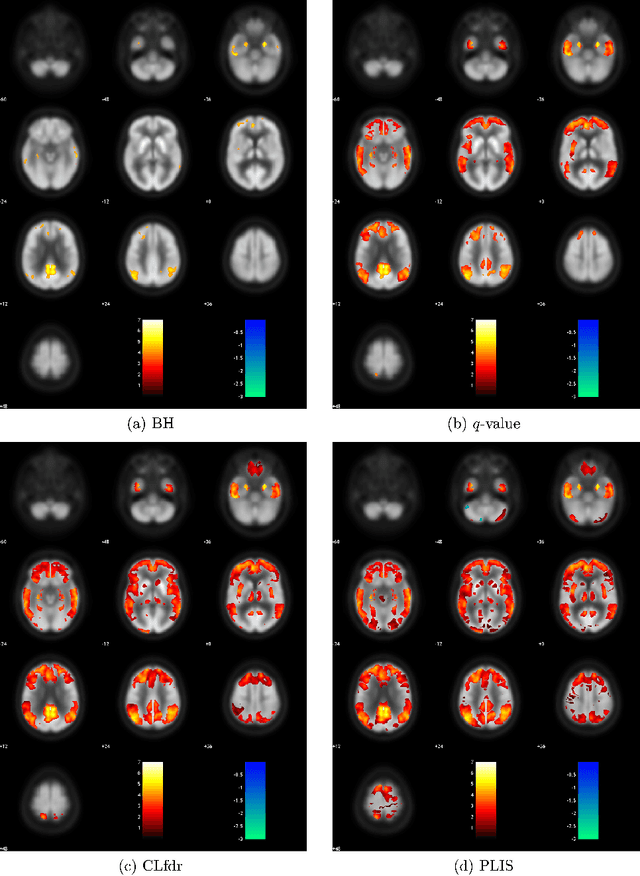

Abstract:Traditional voxel-level multiple testing procedures in neuroimaging, mostly $p$-value based, often ignore the spatial correlations among neighboring voxels and thus suffer from substantial loss of power. We extend the local-significance-index based procedure originally developed for the hidden Markov chain models, which aims to minimize the false nondiscovery rate subject to a constraint on the false discovery rate, to three-dimensional neuroimaging data using a hidden Markov random field model. A generalized expectation-maximization algorithm for maximizing the penalized likelihood is proposed for estimating the model parameters. Extensive simulations show that the proposed approach is more powerful than conventional false discovery rate procedures. We apply the method to the comparison between mild cognitive impairment, a disease status with increased risk of developing Alzheimer's or another dementia, and normal controls in the FDG-PET imaging study of the Alzheimer's Disease Neuroimaging Initiative.